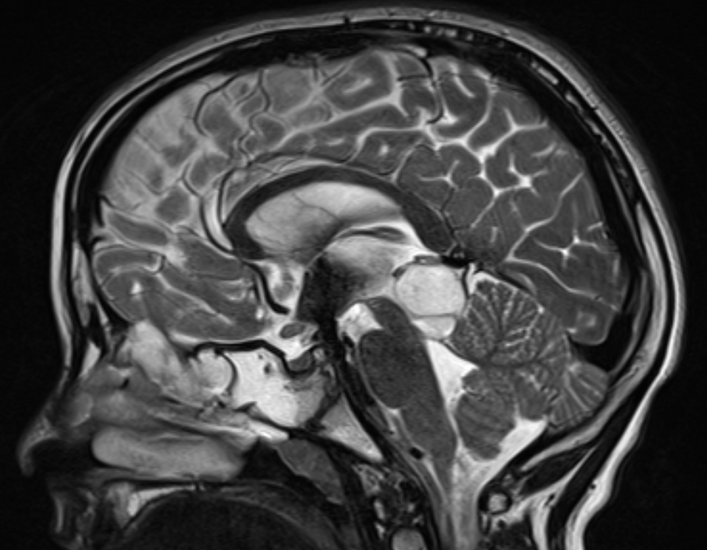

Muhammed is a remarkably brave nine-year-old refugee from Syria. After experiencing months of balance difficulties, followed by severe headaches and vomiting, he was diagnosed with a brainstem glioma located in the midbrain, one of the most delicate and critical areas of the brain.